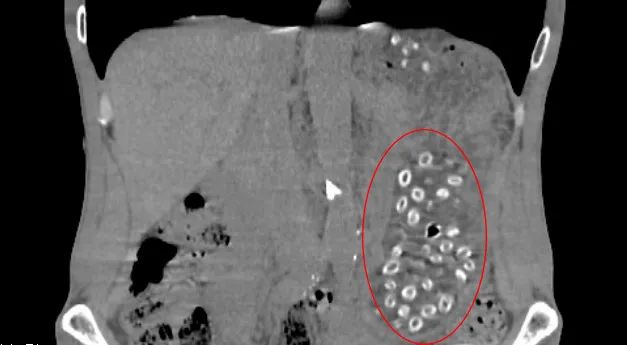

经CT检查后发现胃潴留,胃内可见大量颗粒状物体,密密麻麻,询问得知王大伯近期大量食用杨梅且不吐核,以下影像中呈现的就是没有消化的杨梅核。

入院后,消化内镜室医生在胃镜下实施“异物取出术”,通过异物网篮来回捞了100多次,取出100多颗杨梅核,目测胃里还有几十颗。幸好发现的及时,不然后果不堪设想。